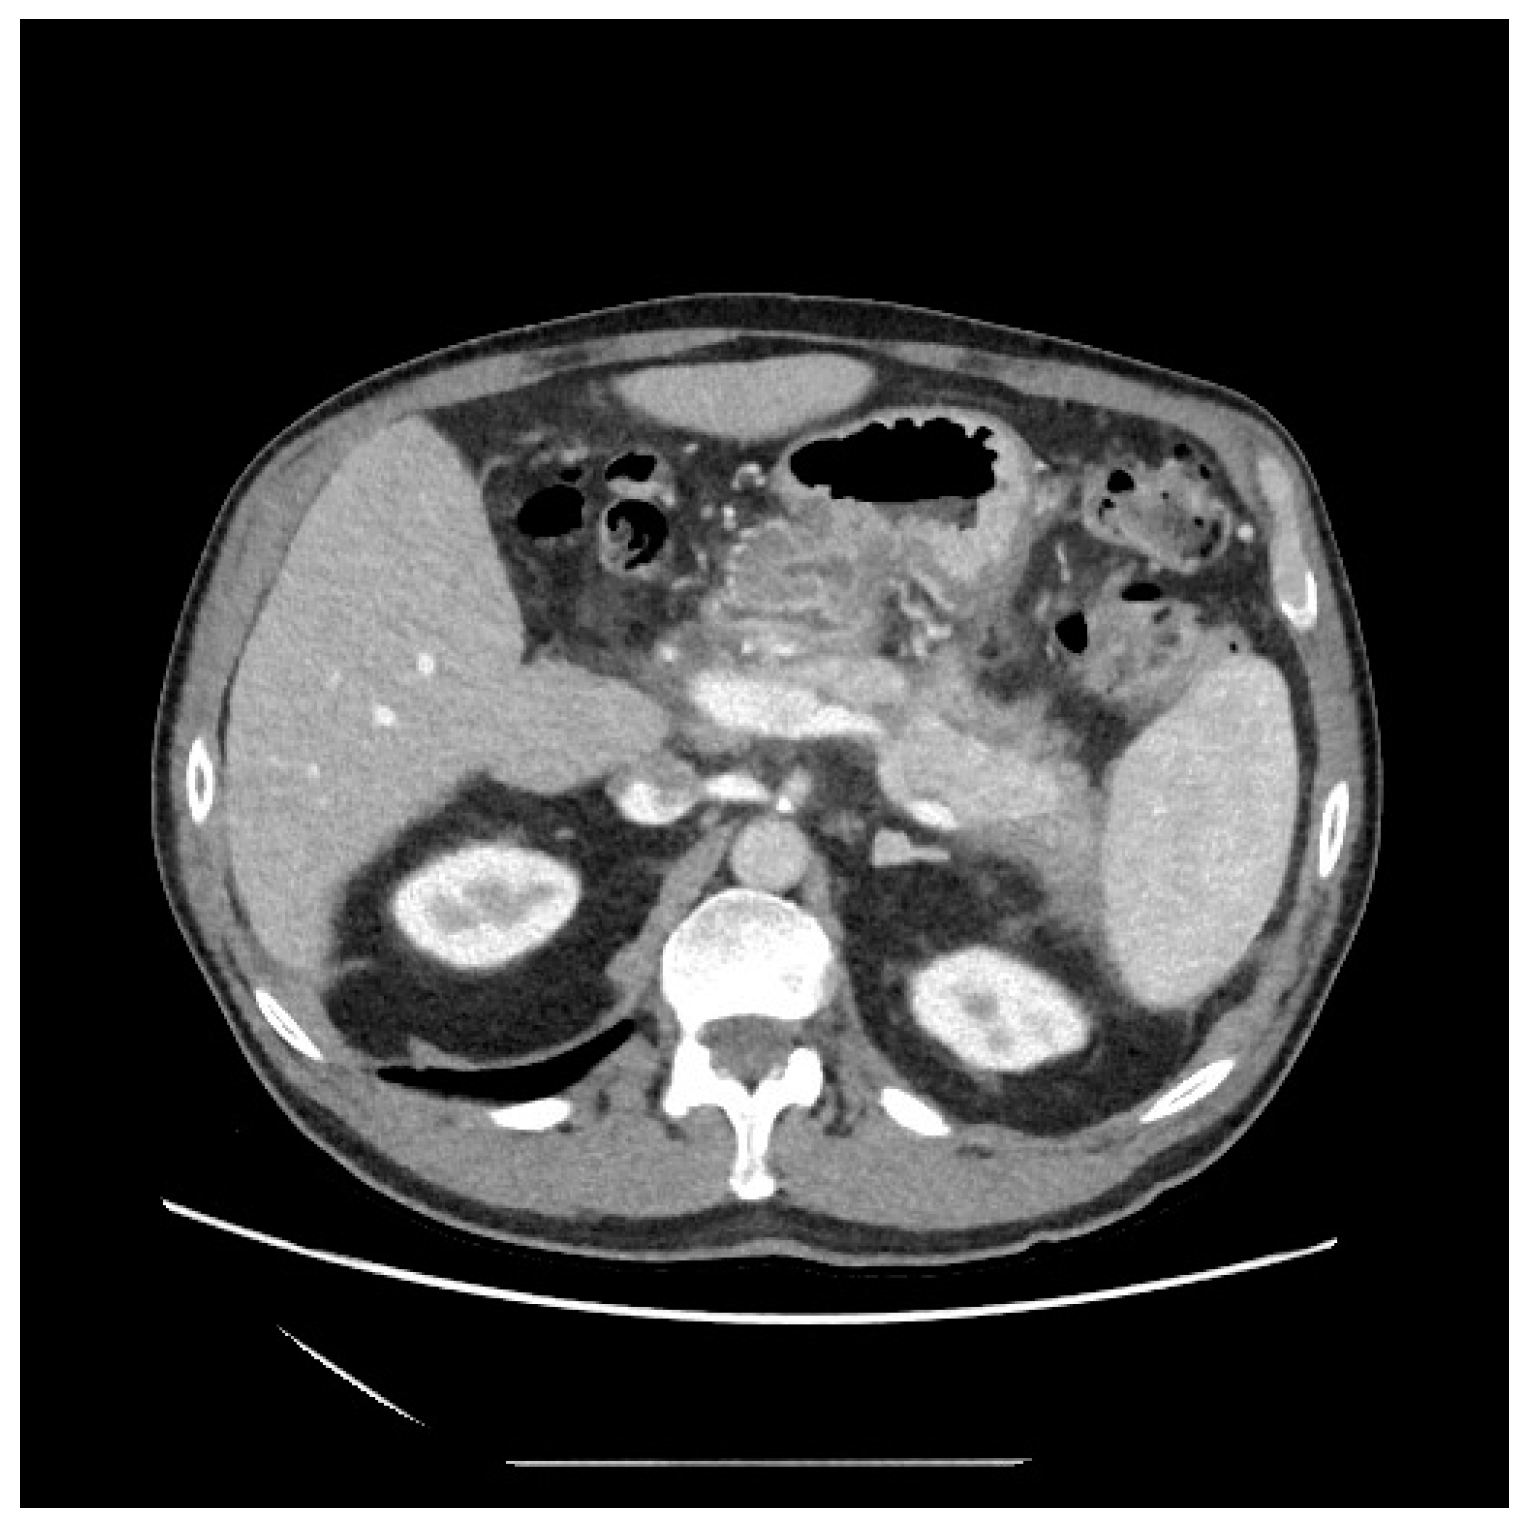

No post-procedural complications were observed, and at a 6th month follow-up, no evidence of recurrence was highlighted (Figure 4).

Figure 4.

CT-scan at 6th month follow-up, showing the complete resolution of necrosis.